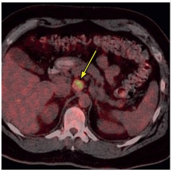

PET Scan

The distal esophagus was intensely FDG avid Pet scanning (SUV 6.2).

The lymph node was also intensely FDG avid (SUV 8.3)